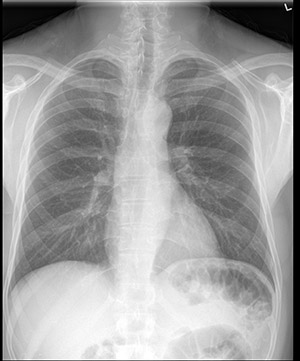

标准胸部 X 光检查